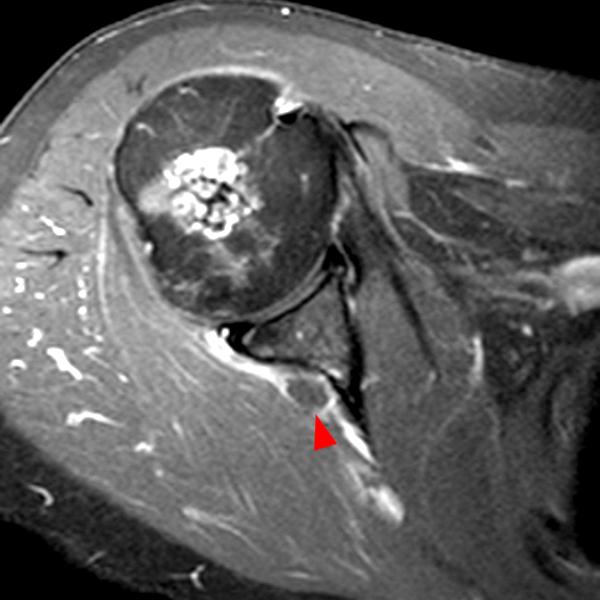

Shoulder Cysts Mri

From mavink.com

Shoulder Cysts Mri Back Shoulder Cyst A paralabral cyst, or ganglion cyst, is a fluid collection arising from the shoulder’s ball and socket joint. Let’s start by looking at the four most common causes of a lump on the back of your shoulder and how to treat them. A sebaceous cyst on the shoulder, aka epidermoid shoulder cyst is a small sac filled with keratin, a. Back Shoulder Cyst.